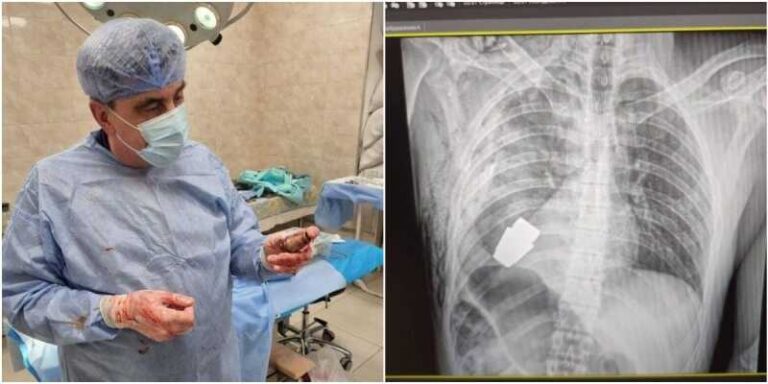

Komplekovana operacija izvedena je u Kijevu kada je u vrlo teškim uvjetima iz tijela ukrajinskog vojnika uklonjena neeksplodirana granata, potvrdili su visoki zvaničnici u Kijevu.

– Hirurzi su uklonili eksplozivno sredstvo koje se nalazilo tik ispod srca povrijeđenog vojnika, dok su se dva sapera pobrinula da operacija bude provedena sigurno – kazala je Hanna Maliar, zamjenica ukrajinskog ministra odbrane.

Objavljena je fotografija na kojoj se vidi rendgenska snimka granate u tijelu vojnika.

– Vojni doktori su izveli su operaciju uklanjanja VOG granate, koja se nije raspala, iz tijela vojnika – napisala je Maliar u objavi na Facebooku.

Anton Geraščenko, savjetnik ukrajinskog ministra unutrašnjih poslova, rekao je da je tim sapera neutralizirao streljivo i opisao postupak kao onaj koji će “ući u medicinske udžbenike”.

U objavi na društvenim mrežama stoji da je operacija izvedena bez upotrebe elektrokoagulacije – uobičajene metode u kojoj se električna struja koristi za kontrolu krvarenja tokom operacije – jer bi “streljivo moglo detonirati bilo kada”, piše BBC.

Jedna fotografija prikazuje hirurga koji drži eksploziv nakon obavljene operacije.